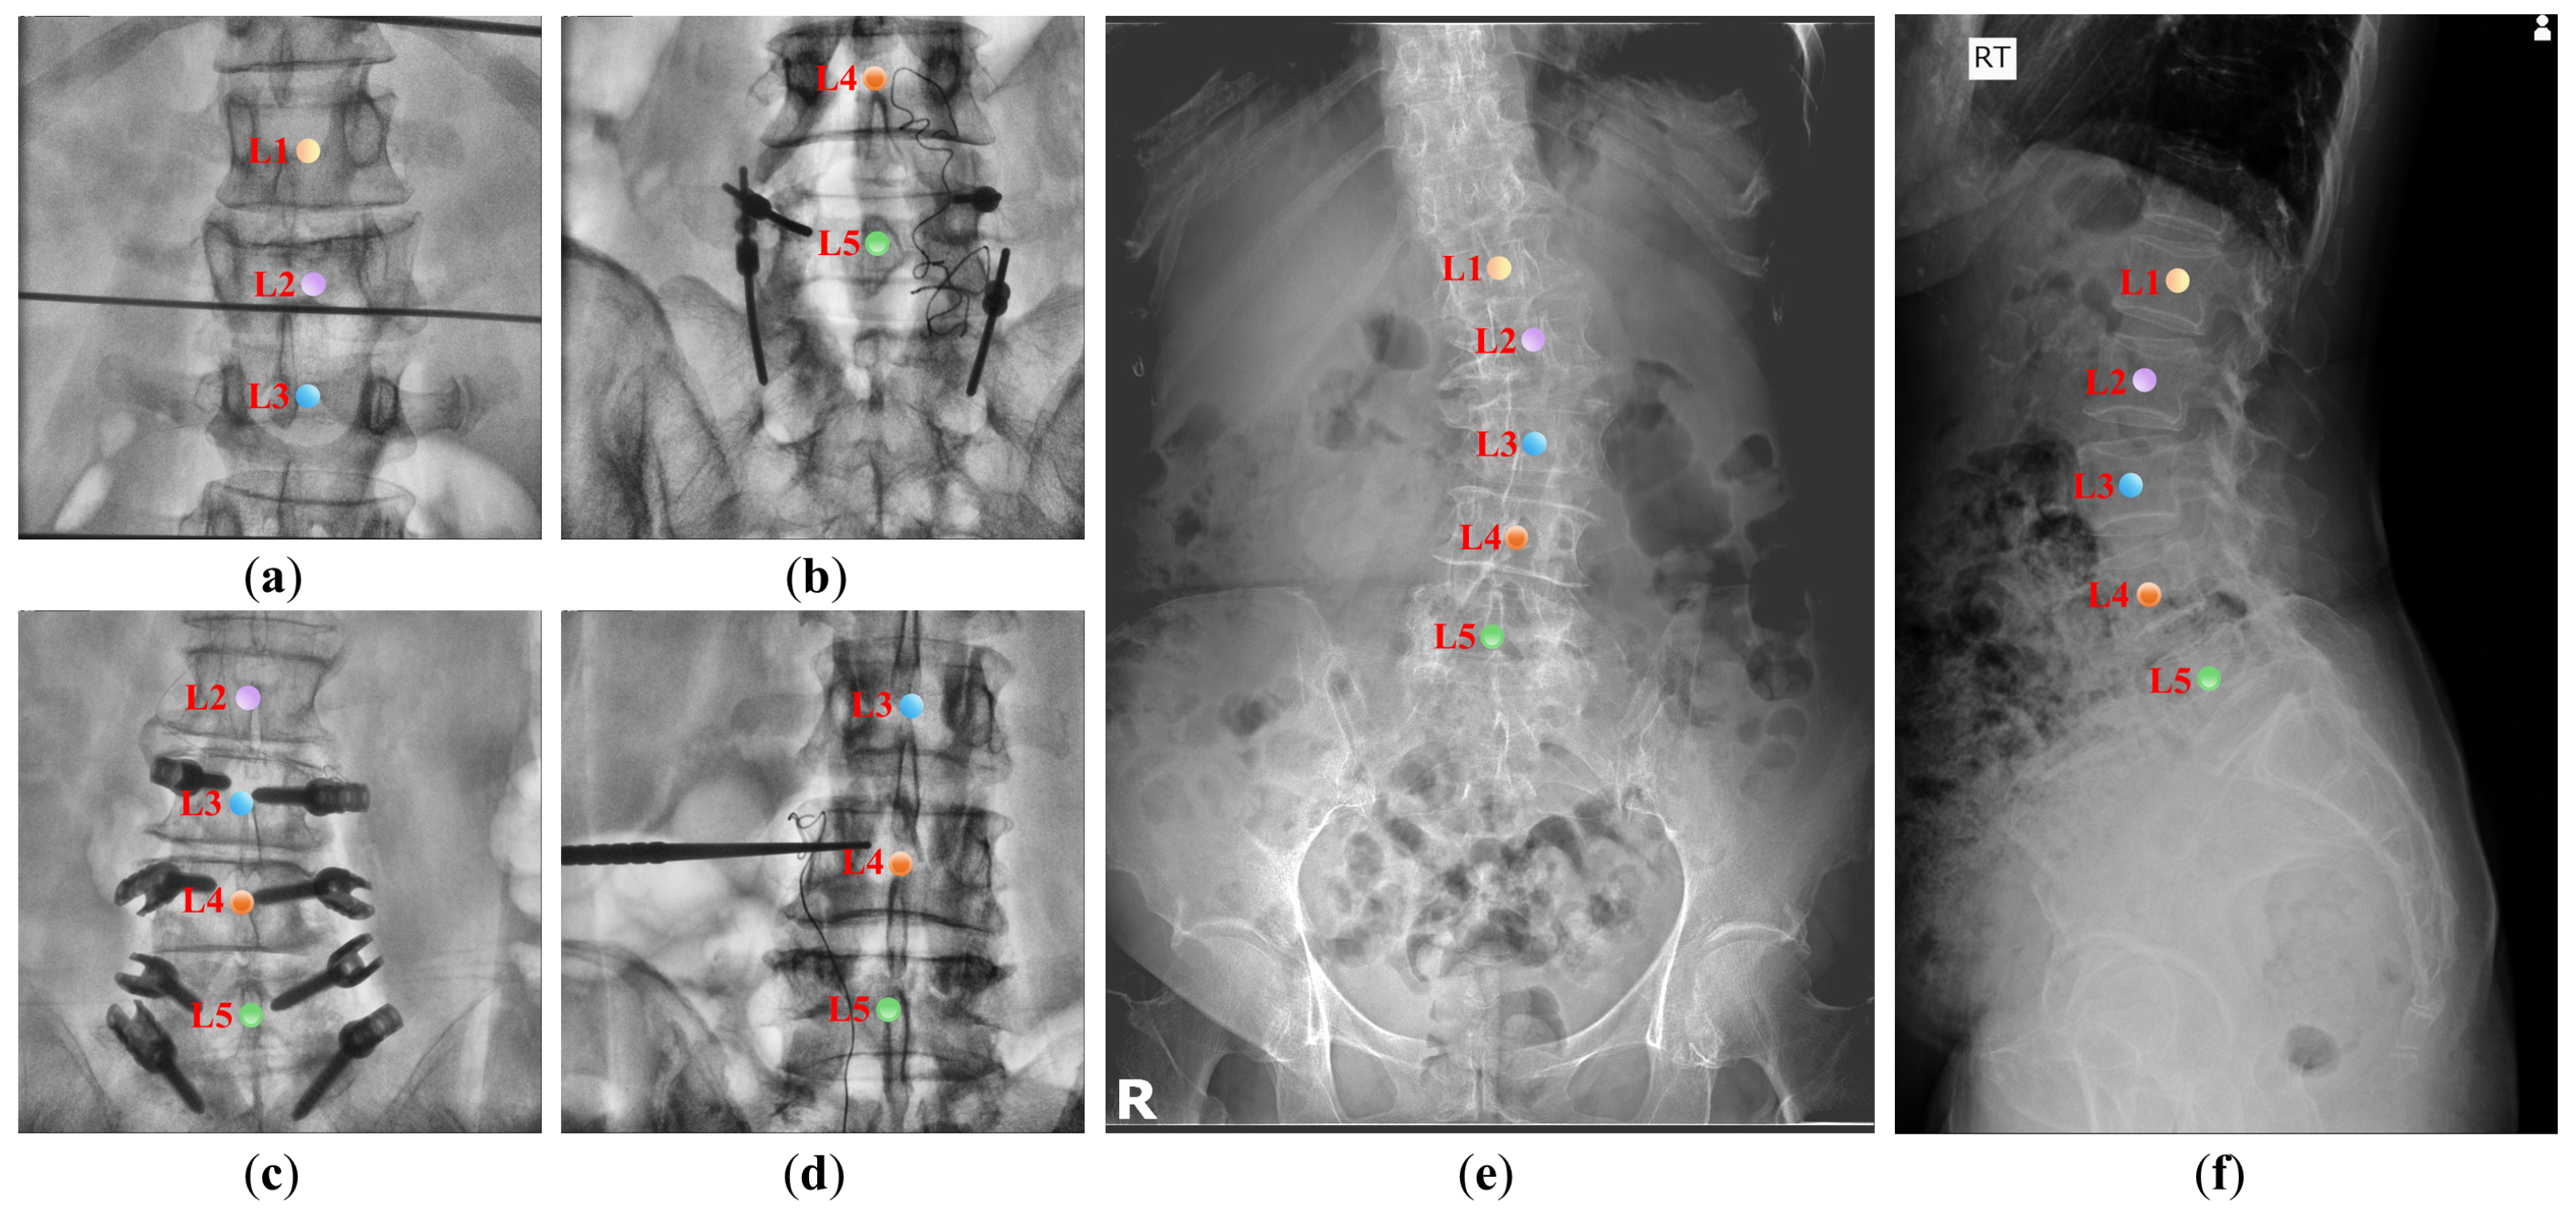

Figure 1.

The challenge of automatically identifying vertebrae in the lumbar spinal image. (a–f) are lumbar spine X-ray images from two different datasets, demonstrating challenges including variations in fields of view, abundant interference information, variability in numbers of vertebrae, similar visual features of vertebrae, and variations in vertebral shape and size due to individual differences. The center points of different categories of vertebrae are distinguished by different colors.